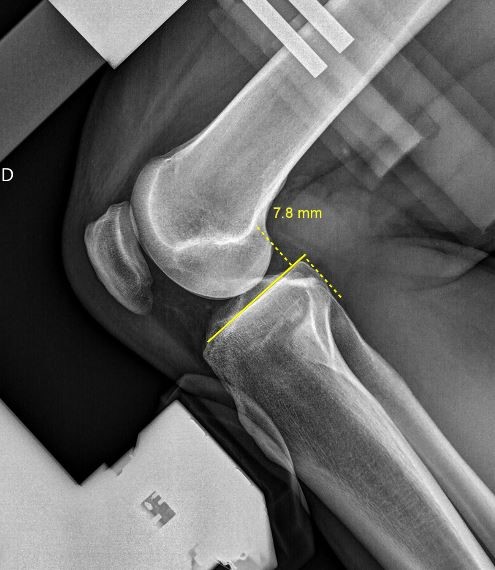

Le Telos Stress est un appareil permettant de réaliser les examens en salle de radiologie visant à tester la stabilité et quantifier la laxité des ligaments des  articulations.

Cet Appareil est particulièrement adapté à l’étude fonctionnelle des ligaments croisés des genoux LCA et LCP et ligaments collatéraux des chevilles avant toutes décisions thérapeutique ou chirurgicale.

La méthode est précise et reproductible car le positionnement est toujours identique et la force exercée est étalonnée.

Les mesures réalisées sur les images radiographiques permettent d’obtenir un diagnostic précis pour le prescripteur.